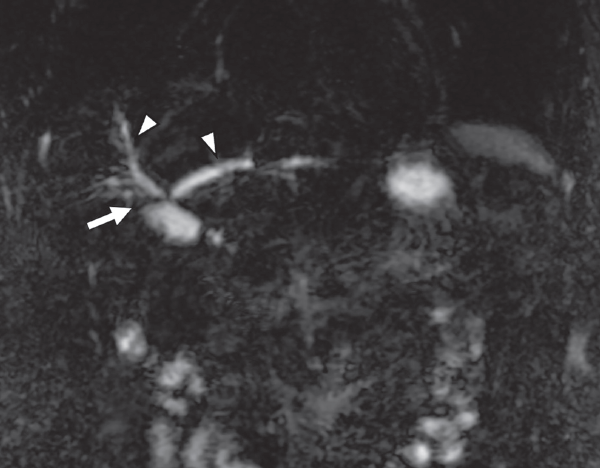

Ante la posibilidad moderada de coledocolitiasis y pancreatitis aguda, se solicitó colangiorresonancia en donde se observaron imágenes compatibles con derivación bilioyeyunal antecólica con anastomosis del hepático derecho anterior, posterior e izquierdo independientes (figuras 1 y 2), y datos de colangitis. Se observó dilatación de la vía biliar distal en el segmento IV con retracción de la cápsula focal (figura 3).

Imágenes: A. Lomas Guim et al.

Sitio de anastomosis biliodigestiva hepatoyeyunal (flecha). Conducto hepático derecho anterior y conducto hepático derecho anterior y conducto hepático izquierdo (cabezas de flechas).

Figura 2 RM coronal T2 finos